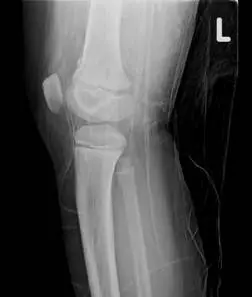

10 歲男童從滑梯跌落以左膝著地,由於膝部疼痛腫脹,父母帶他來急診求診,並接受 X光檢查,由此 X光影像,顯示他發生了何種的生長板傷害?

本題考的是兒童生長板骨折(physeal fracture)的 Salter-Harris 分類。10 歲男童從滑梯跌落以左膝著地,X 光影像顯示骨折線通過生長板(physis)並延伸至幹骺端(metaphysis),此為 Salter-Harris 第二型的典型表現。

影像一(側位,oblique view): 左膝關節 X 光側位,可見遠端股骨(distal femur)或近端脛骨(proximal tibia)生長板區域有骨折線。骨折線沿生長板水平走向,並伴隨一個三角形幹骺端骨片(metaphyseal corner fragment,又稱 Thurston Holland fragment),此為骨折線從生長板轉向幹骺端所造成的特徵性碎片。骨骺(epiphysis)本身結構完整,關節面未受波及。

影像二(正位,AP view,標記 L): 左膝正位影像,可更清楚看到骨折線同時涉及生長板與幹骺端的一角,骨骺端無明顯骨折線延伸,關節腔無明顯異常。整體影像符合骨折線通過生長板 + 幹骺端角落的 Salter-Harris 第二型特徵。